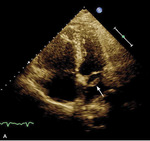

Rycina. Skrzeplina (strzałki) przechodząca do lewego przedsionka uwidoczniona w projekcji 4-jamowej (A) oraz zmodyfikowanej przymostkowej w osi krótkiej (B).

Obraz echokardiograficzny ujawnił typowe dla przeciążenia prawej komory powiększenie jej wymiaru, skrócenie czasu akceleracji wyrzutu płucnego z tzw. zazębieniami na ramieniu zstępującym oraz hiperkinezę wolnej ściany prawej komory z hipokinezą podstawnych jej segmentów i TAPSE 12 mm. Jednak najważniejszą obserwacją było stwierdzenie nieprawidłowego echa w jamie prawego przedsionka, echa odpowiadającego skrzeplinie wklinowanej w przetrwały otwór owalny (PFO) i przechodzącej do lewego przedsionka (rycina).